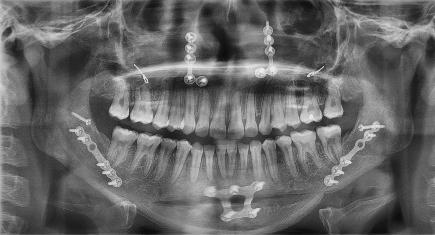

Figura 7. Lefort I. Figura 8. Osteotomía sagital. Figura 9. Mentoplastía. Figura 10. Cefálica de progreso. Figura 11. Panorámica de inicio.

Segunda fase quirúrgica de impactación maxilar Lefort I, 4 mm, (Figura 7), se realizó la cirugía mandibular que consistió en la osteotomía sagital de la rama bilateral de avance, 9 mm (Figura 8), se hizo la cirugía del mentón con la mentoplastía de avance 4 mm, (Figura 9) y una fase postquirúrgica de detallado y retención.

Estudios de progreso

Fueron realizados después de 1 año y 2 meses de haber iniciado el tratamiento y después de la cirugía. En los estudios radiológicos tenemos que en la radiografía lateral de cráneo las placas utilizadas para consolidar la fijación de los maxilares, la corrección de las relaciones esqueléticas en la Figura 10. En la panorámica inicial se señalan los gérmenes de los terceros molares (Figura 11) y en la Figura 12, la realización de las exodoncias de órganos dentarios 18, 28, 38 y 48.